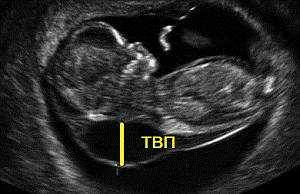

Итак, что такое воротниковое пространство у плода? Это ультразвуковой маркер, указывающий на возможные хромосомные аномалии. Толщина воротникового пространства (ТВП) — это ширина области в шейном отделе позвоночника, заполненная подкожной жидкостью. Термин «воротниковое пространство» введен в 1996 году и используется в скрининговых исследованиях во многих развитых странах.

Исследование воротниковой зоны плода проводится с 11 по 13 недели беременности, во время первого УЗИ. В этот период результаты наиболее информативны. Ранее 11 недель исследование нецелесообразно, так как плод слишком мал. После 14 недели лимфатическая система начинает поглощать жидкость, и этот показатель теряет диагностическую ценность.

Толщина шейно-воротниковой зоны у плода измеряется с помощью трансабдоминального или трансвагинального ультразвукового исследования. Чаще используется трансабдоминальное УЗИ; трансвагинальный метод применяется, если первый не дает полной информации. Некоторые специалисты комбинируют оба подхода для более точной оценки.